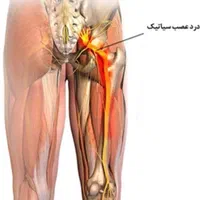

مرکز تخصصی اصلاح ناهنجاریهای اسکلتی با بیش از 15 سال تجربه درخشان زیر نظر متخصص دارای مدرک FTC از مراکز انگلیس و امارات ✅ خدمات ما: • درمان کف پای صاف و قوسدار • اصلاح پای ضربدری و پرانتزی • درمان گودی و دیسک کمر . گودی کمر و قوز • رفع درد زانو و مفاصل • درمان آرتروز و شانه یخ زده • بهبود واریس و سلولیت ویژگیهای منحصر به فرد ما: • ارائه روش اختصاصی براساس شرایط هر فرد • استفاده از متدهای نوین و علمی • پشتیبانی مستمر در طول دوره درمان • ارائه گزارش پیشرفت ماهانه شرایط پرداخت منعطف: • امکان پرداخت اقساطی • تخفیفهای ویژه سازمانی ☆ قیمت هر جلسه یکو نیم میلیون (۱/۵۰۰/۰۰۰ تومان) دوره های (۸جلسه)، (۱۶ جلسه)، (۲۴ جلسه)، (۳۰جلسه)، (۳۶ جلسه) و (۴۲ جلسه) آدرس: سبزه میدان، انتهای پیغمبریه، ساختمان هانا، مجموعه هانا ☆ برای مشاوره حضوری و تعیین وقت ؛ (نام و نام خانوادگی و شماره تماس) خود را در چت دیوار ارسال کنید و یا به شماره آگهی اس ام اس کنید. ☆ عزیزان هر سوالی داشتین از ساعت 11 صبح الی 10 شب تماس بگیرین در خدمتتون هستم. دکتر شاهمحمدی سلامتی شما، تخصص ماست